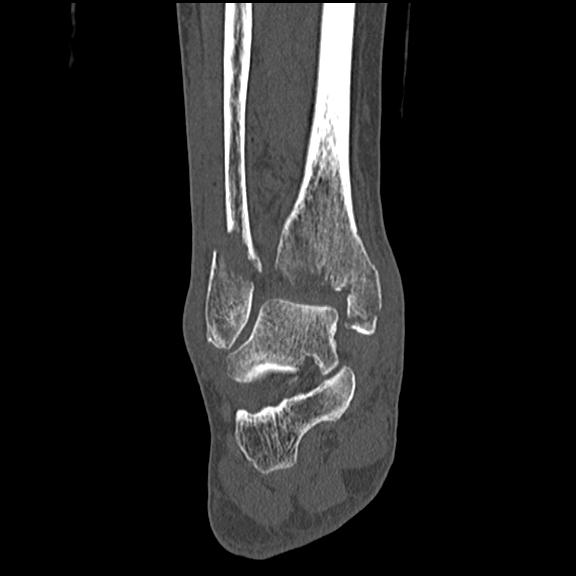

102755 1/4 2R 1/15 2R 右足関節 68歳女性 右三果脱臼骨折